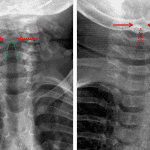

Age: 8 months

Sex: Male

Indication: Stridor

- Loss of shouldering of the subglottic airway

- Ballooning of the hypopharynx

- Croup (laryngotracheobronchitis)

Loss of shouldering of the subglottic airway and ballooning of the hypopharynx, likely relating to croup.

No evidence of epiglottitis.

No retropharyngeal thickening.